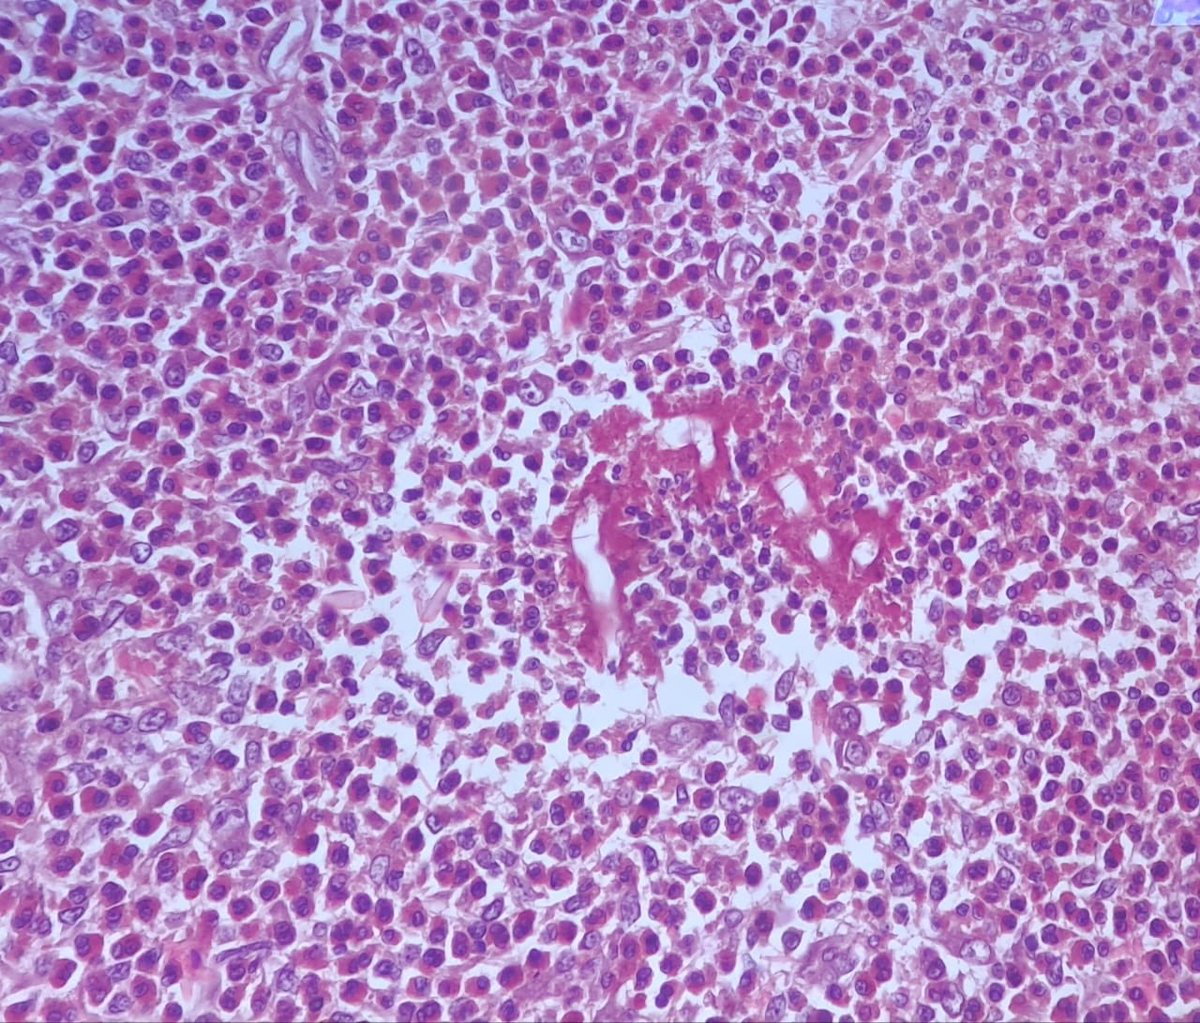

يظهر هذا النوع من الفطريات في جهاز الاشعة التلفزيونية عند الكشف عن المريض كانه عبارة عن خلايا سرطانية ويشخص للوهله الاولى احتمال ورم سرطاني ولكن عند التشخيص النسيجي الصحيح يظهر الفطر بشكل واضح كما بالصورة التالية

لو ركزنا في الصورة حنلاقي انو ما يمز هذا الفطر بالنسيج انو يكون منطقة حمراء حولة وهو ما اكده العالمان سيلندور وهوبلي كدليل واضح وتاكيد على الفطر لاحظو الصورة ركزو بالمنطقة الفاضية هذا الهيفا للفطر واضحة

في الصورة التالية نلاحظ بشكل واضح اللون الاحمر حول الهيفا للفطر لاحظو 👇👇